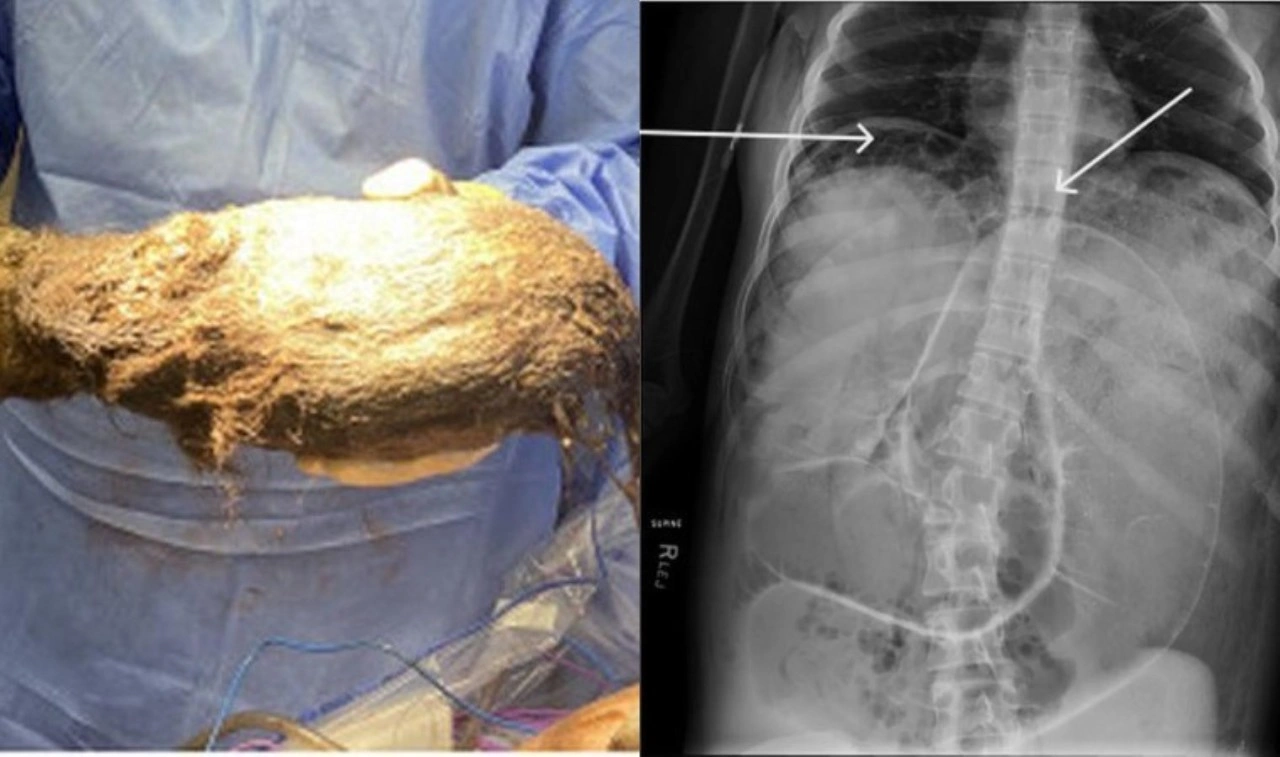

Ancak, yapılan kontrollerin ardından daha fazlasının olduğu ve bağırsaklarında trikobezoar olarak bilinen gastrointestinal sistemde biriken büyük bir tıkanıklık olduğu anlaşıldı.

Karmaşık bir prosedürün ardından doktorlar, kızın midesinden 2,468 gram ağırlığında bir kıl yumağı çıkardılar.